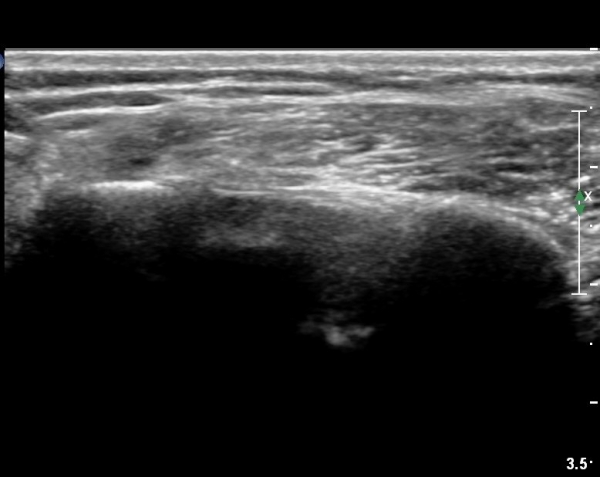

ȸÀü±Ù°³°£°Ý(rotator cuff interval) Ⱦ´Ü¸é°Ë»ç¿¡¼­ Á¡¾×³¶ÀÇ ºÎÁ¾ÀÌ °üÂûµÈ´Ù(»çÁø 3).